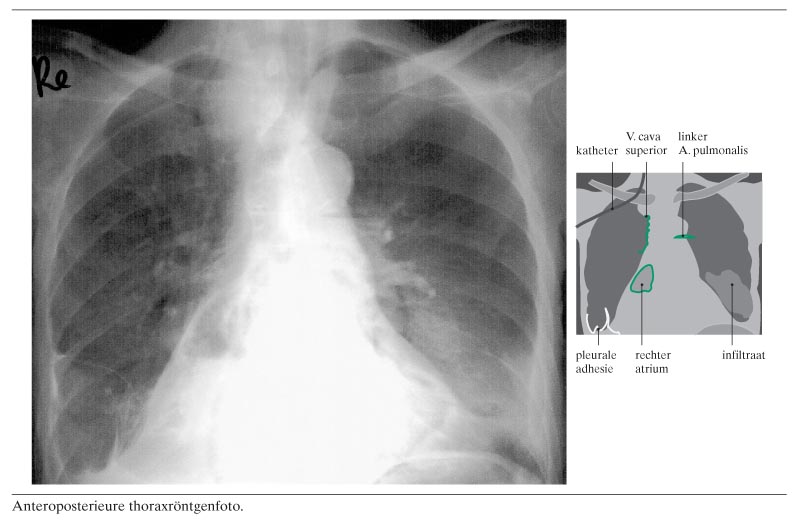

Een 72-jarige vrouw met een voorgeschiedenis van diabetische nefropathie kreeg een centraalveneuze katheter voor hemodialyse. Na plaatsing van de katheter werd een routinethoraxfoto gemaakt en op dat moment collabeerde patiënte. Op de foto was, behalve een foutieve plaatsing van de katheter in de V. jugularis interna, een luchtembolus te zien in het rechter atrium (figuur). Ook waren luchtbellen zichtbaar in de V. cava superior, die daardoor niet meer door een rechte lijn was begrensd, maar komvormige ‘defecten’ vertoonde; verder was er een luchtspiegel in de linker A. pulmonalis. Rechts waren pleura-afwijkingen te zien, overblijfselen van een pleurodese…

De thoraxfoto zoals die is afgedrukt ter illustratie van de door Hermens en Schuurmans beschreven casus (2003:442) vraagt om een reactie. De kwaliteit van de afdruk is zeer matig; volgens ons is de opname niet toereikend als middel om deze – toch belangrijke – klinische diagnose toe te lichten dan wel te onderbouwen. Inderdaad ligt de katheter in de V. jugularis, maar lucht in de V. cava superior is hier niet te zien. Wel is lucht zichtbaar in het gebied van het rechter atrium en van de centrale pulmonale arterie. Over de hartfiguur is ook nog een luchtfiguur waar te nemen: een artefact? Daarnaast is te zien dat er een tracheadeviatie is, mogelijk als gevolg van een (deels) retrosternaal gelegen struma, en dat er een volumeverlies is van de rechter onderkwab en ook van de linker, inderdaad met infiltratie aldaar.

De afgedrukte foto is van mindere kwaliteit dan de door ons geleverde originele foto. Mochten de collegae Heijstraten en Ruijs hiervoor nog interesse hebben, dan zijn we uiteraard bereid een kopie op te sturen van het origineel. Daarop zijn ook de luchtbellen in de V. cava superior goed te zien. Terecht merken de briefschrijvers op dat er meer afwijkingen zichtbaar zijn op de foto (onder andere tracheadeviatie), maar wij achtten dit irrelevant voor deze casus. Het gaat hier om de luchtembolus.

Wij zijn het niet eens met het oordeel dat de diagnose ‘luchtembolus’ op basis van deze foto niet gesteld zou mogen worden. Ook de opmerking dat een dwarse opname, gevolgd door doorlichting, noodzakelijk zou zijn, vinden wij niet reëel. Zoals gezegd in het artikel collabeerde patiënte nadat de foto was gemaakt. Een dwarse opname en doorlichting zijn alleen te realiseren als de patiënt kan staan. In dit geval was dat onmogelijk.